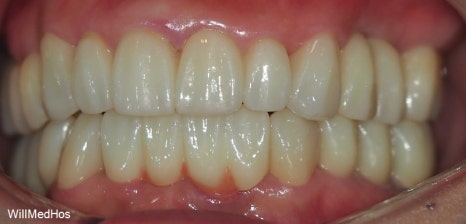

최종 치료 완료된 구강 모습입니다. 앞전의 구강 사진과 비교해보시면 자연스러운 치아의 모습이 완성된것을 확인 할수 있습니다.

전체 최종 치료 기간은 9개월 소요 되었습니다